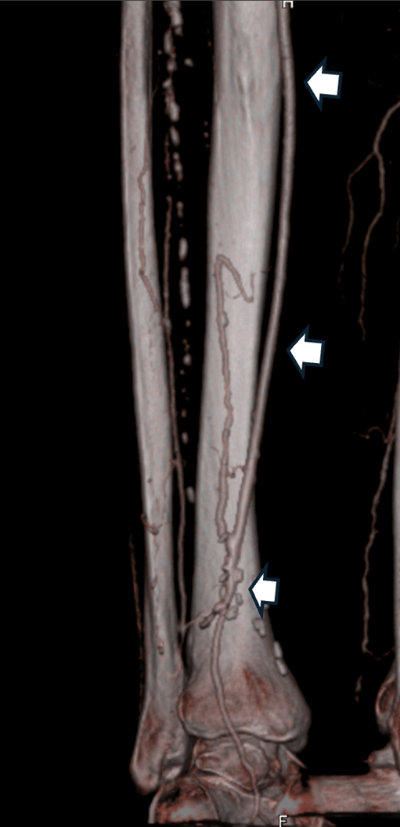

- Cirugía de bypass: se utiliza un injerto (propia vena del paciente o un conducto artificial) para desviar la sangre y saltar la obstrucción. (Fig. 2)

Fig. 2: Bypass distal a nivel del tobillo, con vena safena del mismo paciente (flechas blancas).